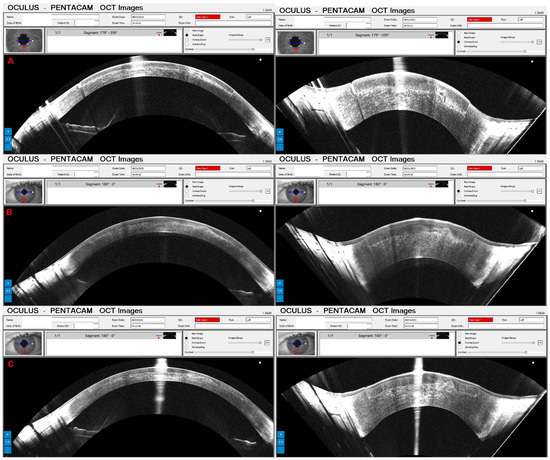

Combined Rotating Ultra-High-Resolution Spectral Domain OCT and Scheimpflug Imaging for In Vivo Corneal Optical Biopsy

1.3. The Pentacam® Cornea OCT